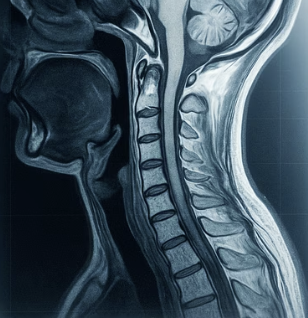

두 질환의 모든 차이점은 바로 '무엇이 눌리느냐'에서 시작됩니다. 우리 목뼈 속에는 뇌에서부터 팔다리로 이어지는 신경의 '중앙 고속도로'인 '척수'가 지나가고, 각 층마다 팔과 손으로 가는 '지방 국도'인 '신경근'이 갈라져 나옵니다. 이 두 가지 길의 차이를 이해하는 것이 핵심입니다.

'목디스크'는 튀어나온 디스크가 주로 지방 국도에 해당하는 '신경근' 하나를 누르는 문제입니다. 마치 국도 한 차선에 사고가 나서 그 길이 막히는 것과 같죠. 반면, '경추척수증'은 디스크나 퇴행성 뼈가 자라나 중앙 고속도로인 '척수' 자체를 압박하는 훨씬 심각한 문제입니다. 고속도로 전체가 막혀버리니 그 아래로 향하는 모든 교통이 마비되는 상황과 같습니다.

A. 좋은 질문입니다. 뇌졸중도 손의 기능 장애를 유발할 수 있지만, 보통은 갑작스럽게 발생하며 두통이나 어지럼증, 언어 장애 같은 다른 뇌신경 증상을 동반하는 경우가 많습니다. 반면 경추척수증은 몇 개월에 걸쳐 서서히 증상이 악화되는 특징을 보입니다. 물론 정확한 감별은 반드시 병원에서 MRI 등의 검사를 통해 이루어져야 합니다.